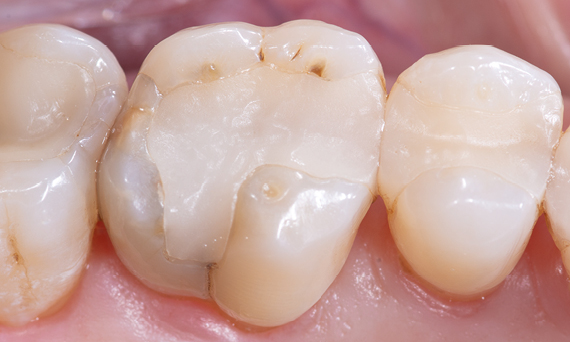

Before: Insufficient fillings in the second quadrant. The restorations were about 15 years old.

After: Chairside-fabricated crowns made from CEREC Tessera (teeth 26/27). Inlays for teeth 24 and 25 made of composite blocks.